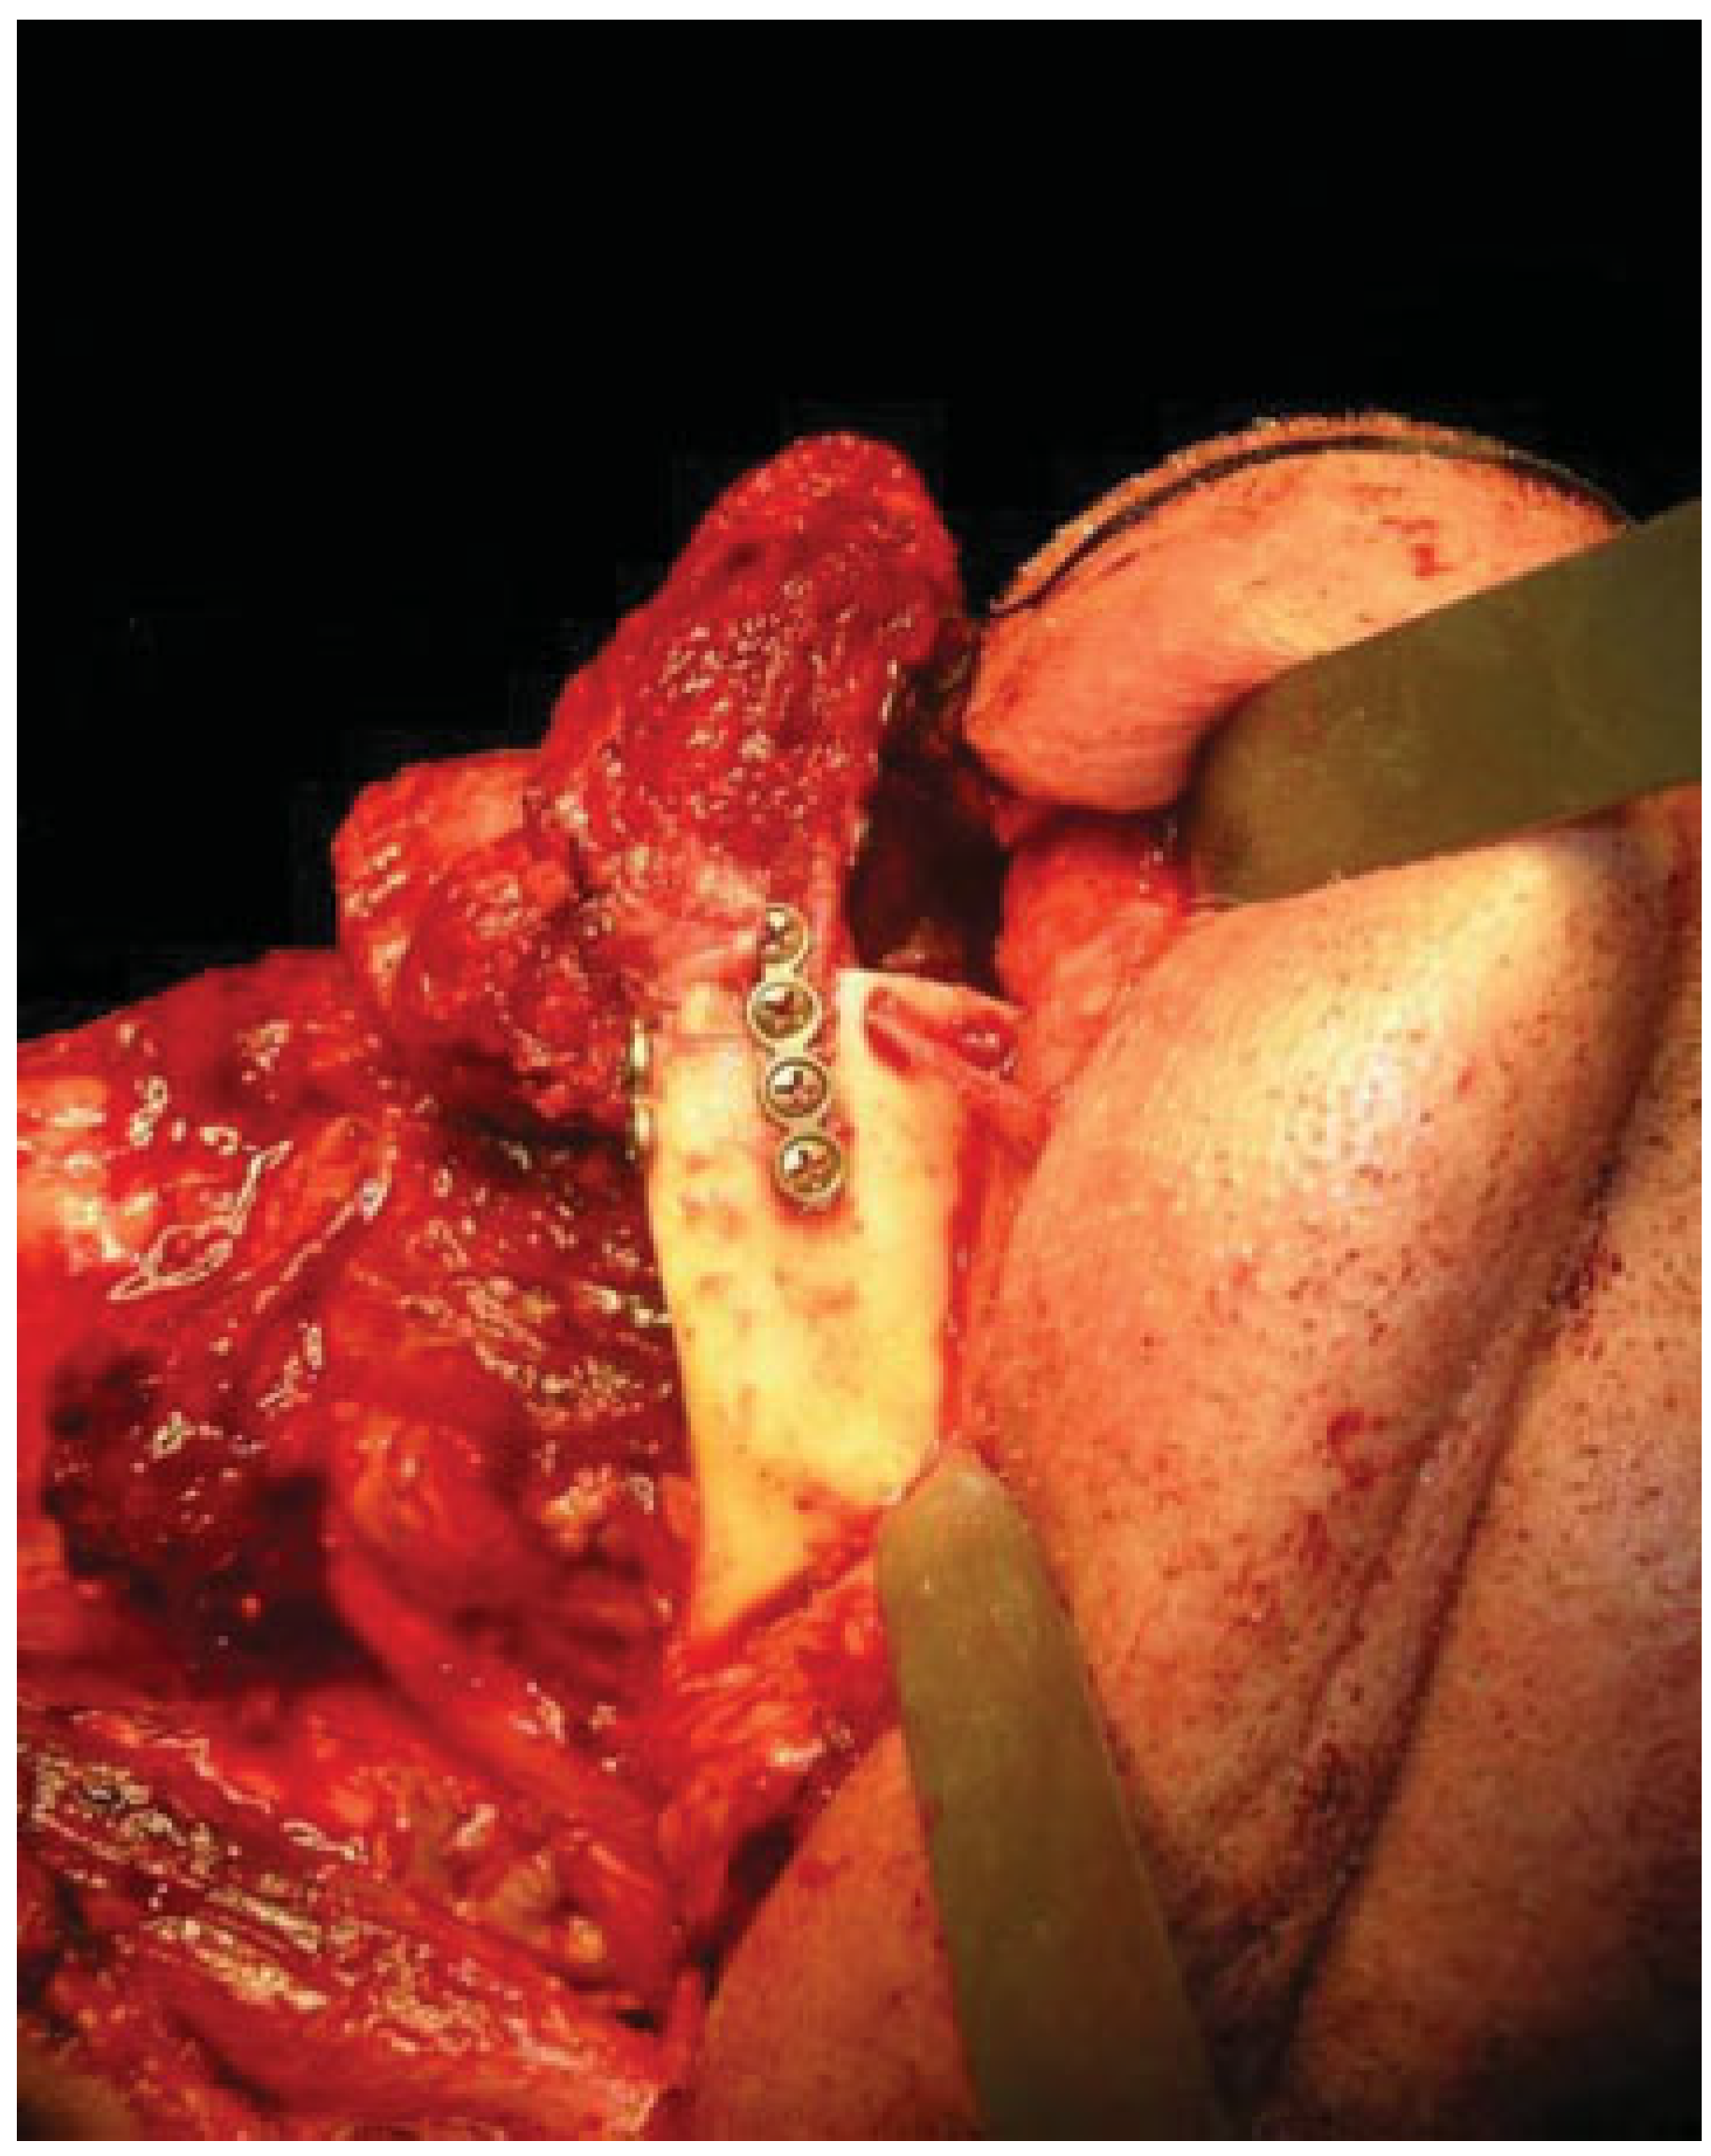

The mandibular resection is performed utilizing a horizontal osteotomy (Figure 1) above the mandibular angle on one side and a stepped body or angle osteotomy on the other side (Figure 2). A silicone template is created to the shape and dimension of the resected mandibular segment. The template is used as a guide to osteotomize the fibula at the donor site to reproduce the middle symphyseal segment of the mandible without shortening the fibula. The flap is then transferred to the recipient site and oriented so that one end will fit in the stepped osteotomy in a key and lock fashion (Figure 3) and the other end of the flap will overlap with the horizontal mandibular osteotomy (Figure 4), allowing room for adjustment in the anterior posterior direction to achieve the desired chin point projection (Figure 5). When the desired projection is achieved—guided by the silicone template—both ends of the flap are marked with a sterile pencil and trimmed using the saw; then miniplates are used to fix the flap in place (Figure 6).

Our technique is unique as it allows flexibility in adjusting the chin point projection to give the best possible aesthetic outcome. Trimming of the flap ends is performed at the recipient site to reduce the risk of short flap, but should this happen, the overlap at the horizontal osteotomy side will allow for compensation (Figure 4). Moreover, the greater surface contact area at the horizontal osteotomy side together with the key and lock fitting at the stepped osteotomy side (Figure 3) increase the stability of the flap and reduce the risk of rotation, hence allowing the use of miniplates for fixation; this in return allows room for placing more than one plate on each side, adding to the stability. The use of miniplates for fixation also facilitates the placement of implants in future rehabilitation.

Figure 3. Fibular flap fitting in key and lock fashion into the stepped mandibular osteotomy.